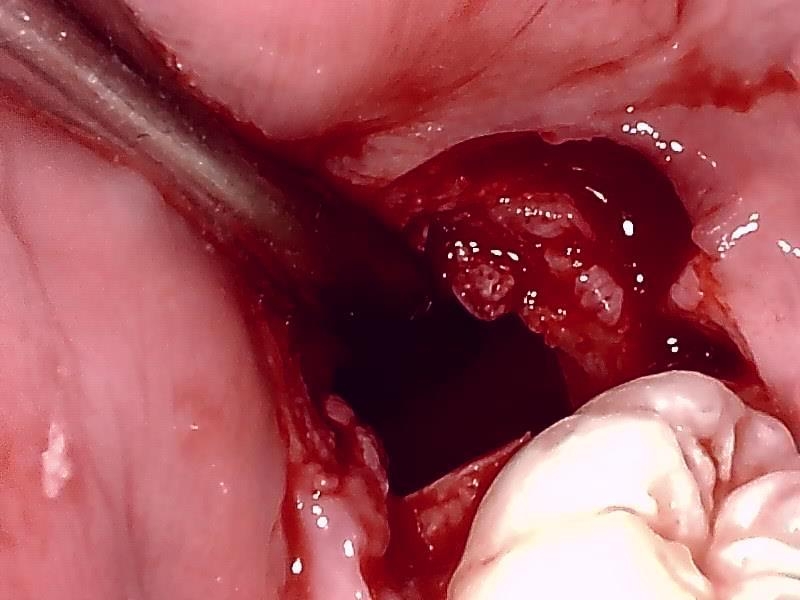

抜歯窩

縫合